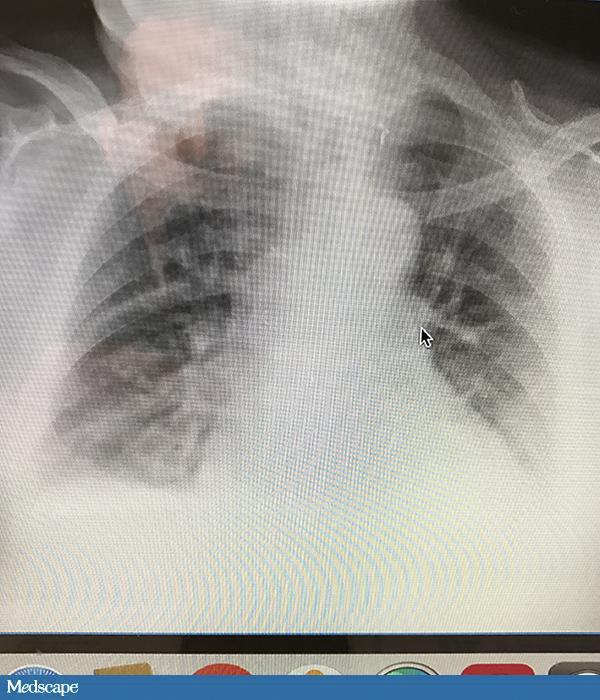

79 岁男性,病史复杂,包括心脏骤停、气管造口术后呼吸衰竭、经皮胃造口术置管(PEG)、慢性阻塞性肺疾病和糖尿病。近期患者从急性护理医院转入一家看护机构。转入后 6 天,患者出现间歇性干咳。生命体征平稳。无发热,呼吸节律正常,氧饱和度无变化。听诊闻及双肺底部湿罗音。便携式胸片示“肺右上叶轻微渗出”。患者白细胞为 12100 /µL,并未偏离正常值。医生开处万古霉素和头孢他啶 7 天。抗生素使用管理部门人员 48 小时后看到病例,此时应给出怎样的建议?

患者无发热、脓痰、呼吸急促或氧饱和度变化,诊断肺炎的证据不足。肺炎的诊断需要结合临床特征、实验室检查和放射科结果,不能只基于胸片发现就下诊断。如果患者发生肺炎,应该是医院内感染,所以没有必要增加非典型病菌的覆盖。如果确实是肺炎,且没有培养出甲氧西林耐药的金黄色葡萄球菌,停掉万古霉素是合理的处理。但缺少微生物诊断时,应使用覆盖假单胞菌的药物治疗一个周期。